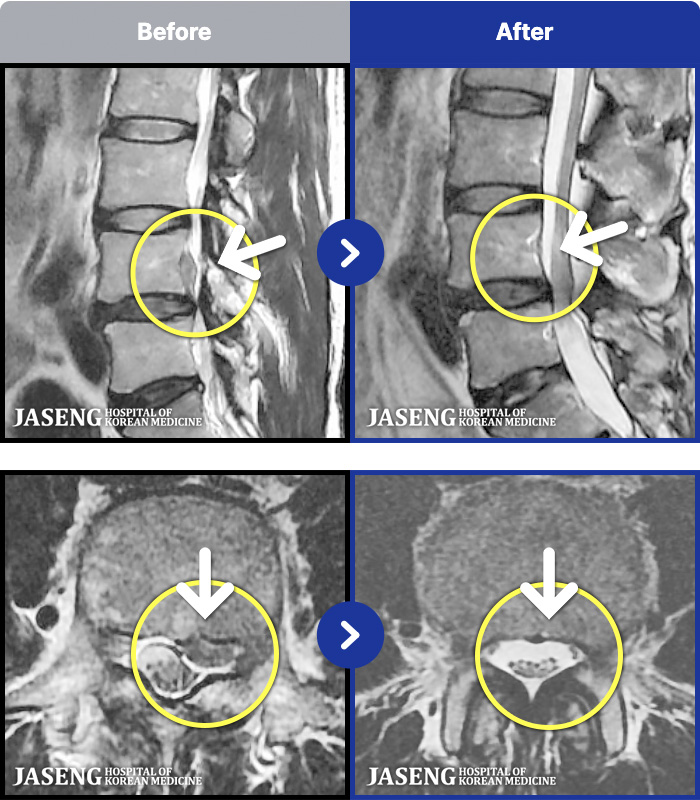

MRI ġ

54 MRI ũ ʸ Ȯϼ.

[Կñ:25.02.14~25.10.04]

[_㸮ũ] кο ٸ ٸ ٷϷ Ÿ.

No.51

ȸ 121

2026.01.06